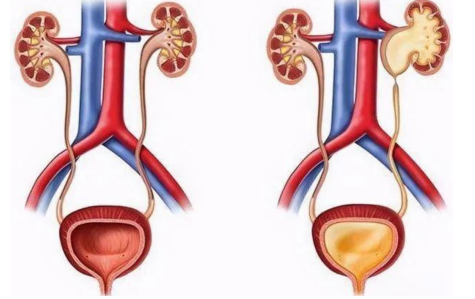

输尿管狭窄是指输尿管管腔的局限性缩窄,导致尿液引流不畅,引起肾积水和肾功能损害。输尿管狭窄可发生在输尿管的任何部位,常见于肾盂输尿管连接部、输尿管中段和输尿管膀胱连接部。输尿管狭窄的程度和长度各不相同,轻者可能仅表现为输尿管轻度扩张和肾积水,重者可导致完全性梗阻和肾功能丧失。

输尿管狭窄的临床表现取决于狭窄的程度和部位。轻度狭窄可能无明显症状,仅在体检或影像学检查时偶然发现。严重狭窄可表现为患侧腰部胀痛、肾积水、尿路感染、肾功能损害等。部分患者可能出现血尿、尿频、尿急、尿痛等症状。